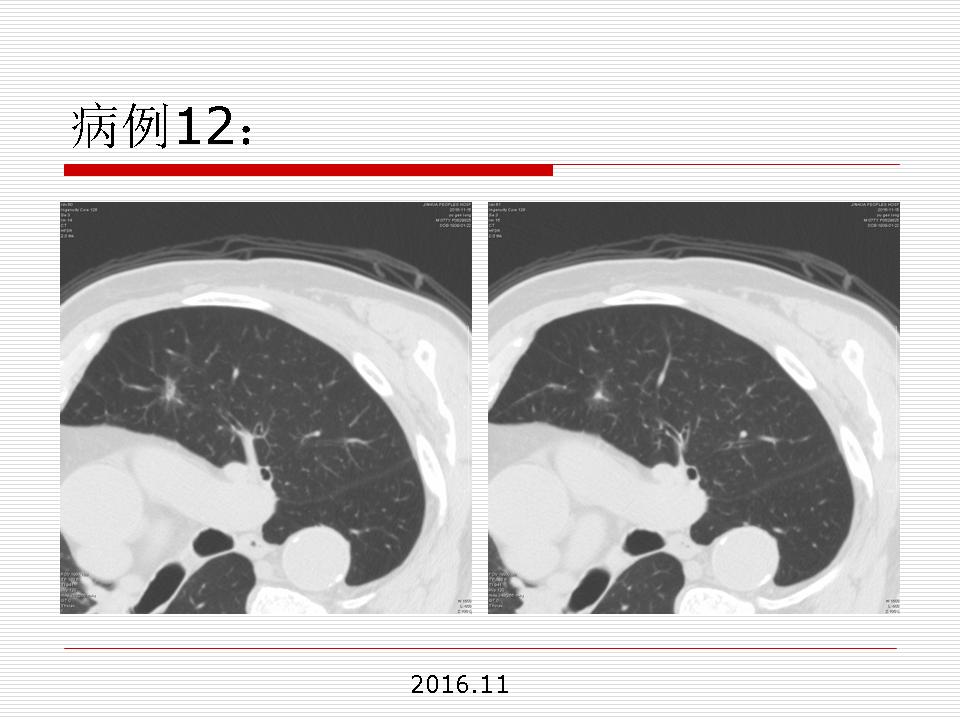

肺部阴影永恒且最重需要鉴别的是:到底是炎症还是肿瘤?但临床的病例中的影像表现难以界定或有些肿瘤特征,同时又有些炎症特点是非常常见的情况。作为临床医生我们怎么去总结分析,并找到之所以是炎症或之所以是肿瘤的细微差别或特点非常重要,也非常有用。2019.12.7浙江省2019年胸心外科学学术年会在宁波召开时,我的临床病例分析与经验总结<那些像肺癌的炎症与像炎症的肺癌>获得在大会交流的机会,以下为该PPT的内容,与你分享,希望对同道有益,有借鉴与启迪。若有探讨与进一不完善的建议,欢迎文末留言讨论: